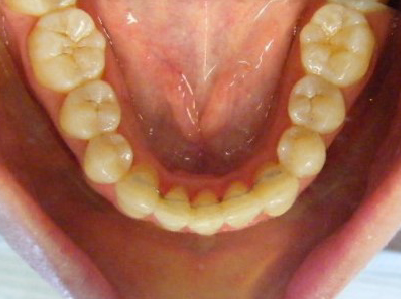

Patient 3: Severe upper and lower crowding.